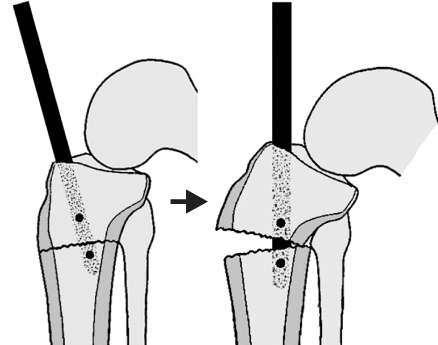

Fig. 3

Medial entry point and laterally directed insertion angle of the nail into the proximal fragment results in valgus malalignment as the nail engages into the distal fragment.

jkfs-22-197-g003.jpg

Fig. 4

Posteriorly directed insertion of the nail into the proximal fragment results in apex anterior angulation at the fracture site when the nail engages into the distal fragment.

Fig. 3 Medial entry point and laterally directed insertion angle of the nail into the proximal fragment results in valgus malalignment as the nail engages into the distal fragment.

Fig. 4 Posteriorly directed insertion of the nail into the proximal fragment results in apex anterior angulation at the fracture site when the nail engages into the distal fragment.